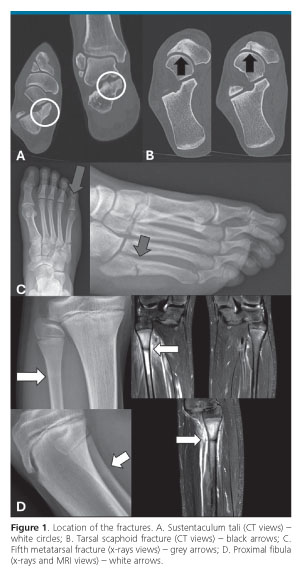

Location of the fracture (figure 1), grade of stress injury, malalignments, treatments performed and time for RTT and RTP are shown in table 3. In group 1 orthopedic treatment was always associated with the application of orthoses after computer-assisted analysis of plantar pressure distribution, as well as hormonal therapy and management of EDs; in those of the second group the same associated predisposing factors were corrected if present.

Stress fractures were diagnosed after an average of 3 weeks from the onset of the symptoms. Second-level imaging (CT and MRI) was always performed, although standard radiographs clearly showed the fracture in the two fifth metatarsal. DEXA scores demonstrated osteopenia in all 5 athletes affected by this injury.